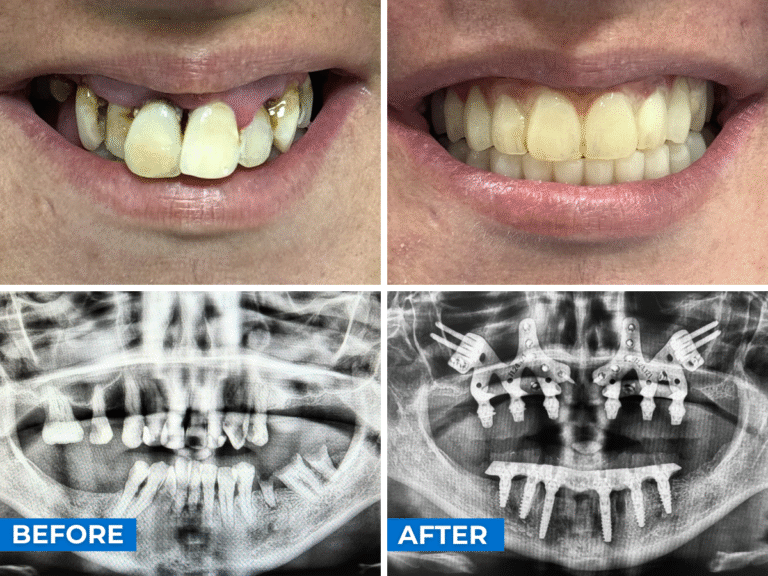

Patientenfall Beispiel B

Ein 40-jähriger Patient mit starker Beweglichkeit aller Zähne, sowohl im Ober- als auch im Unterkiefer. Nach der Durchführung des CT-Scans stellten sie fest, dass im Oberkiefer nicht genügend Knochen vorhanden war, um eine konventionelle Implantatoperation durchzuführen. Darüber hinaus war im Jochbein des zweiten Quadranten – dem linken Jochbein – nur sehr wenig geeigneter Knochen für das Setzen von Jochbeinimplantaten vorhanden.

Daher wurde beschlossen, eine gemischte Oberkieferoperation durchzuführen, d. h. eine Seite mit Jochbeinimplantaten und die andere Seite mit Pterygoidimplantaten. Im Unterkiefer wurde der Eingriff mit sechs konventionellen Implantaten durchgeführt, und 24 Stunden später erfolgte die Sofortbelastung in beiden Bögen.